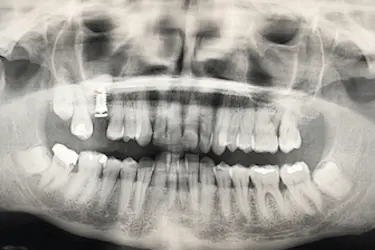

Después de la osteointegración del implante, el paciente acude a revisión para ver el estado del hueso artificial injertado.

La altura del hueso maxilar es ahora de 15 mm lo que ha permitido la colocación del implante dental con poco hueso inicialmente.